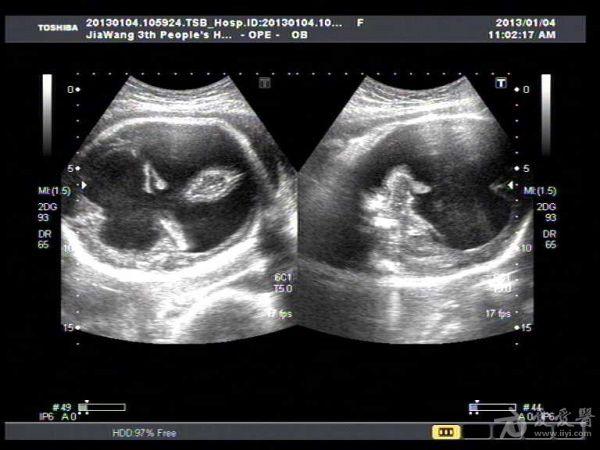

此孕妇听信家人说吃核桃能补脑,吃了两个月核桃来来复查,脑积水更明显。